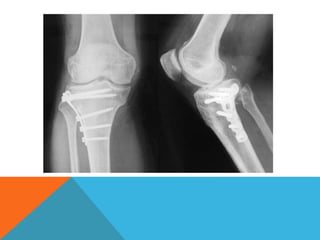

CONDYLAR PLATE

• Has distinct mechanical function

– Maintains the reduction of main intra-articular fragments

– Rigidly fixes the metaphyseal components to diaphyseal shaft,

permitting early movement of the extremity

• Functions as neutralization plate as well as buttress plate. it does act

as compression plate as well.

• Fixed angle of the plate overcomes the coronal plane instability and

prevents consequent collapse.